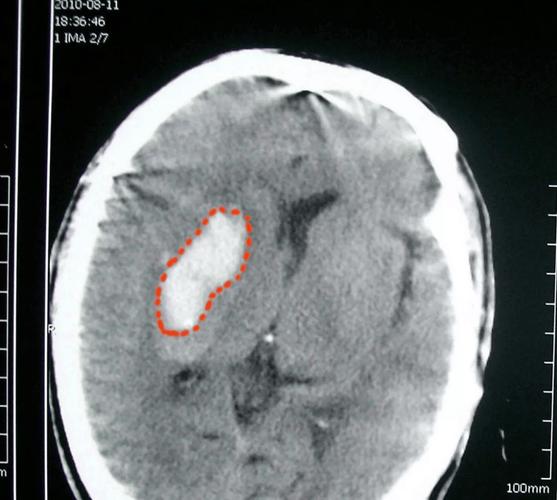

ADC序列(表观弥散系数)—— “DWI的真相”

ADC是DWI的“反向”序列,它直接反映水分子的弥散程度。

- 图片表现:在急性梗死区域,因为水分子运动受限,ADC值会显著降低,图像上显示为黑色低信号。

- 临床意义:ADC是鉴别急性脑梗和伪影的关键!有时候DWI上的亮白斑可能是由于病人头部运动或磁敏感伪影造成的,这时如果ADC上对应的区域也是黑色,就证实了是真正的梗死,如果ADC上是白色(高信号),则DWI的亮白斑很可能是伪影,可以排除脑梗。